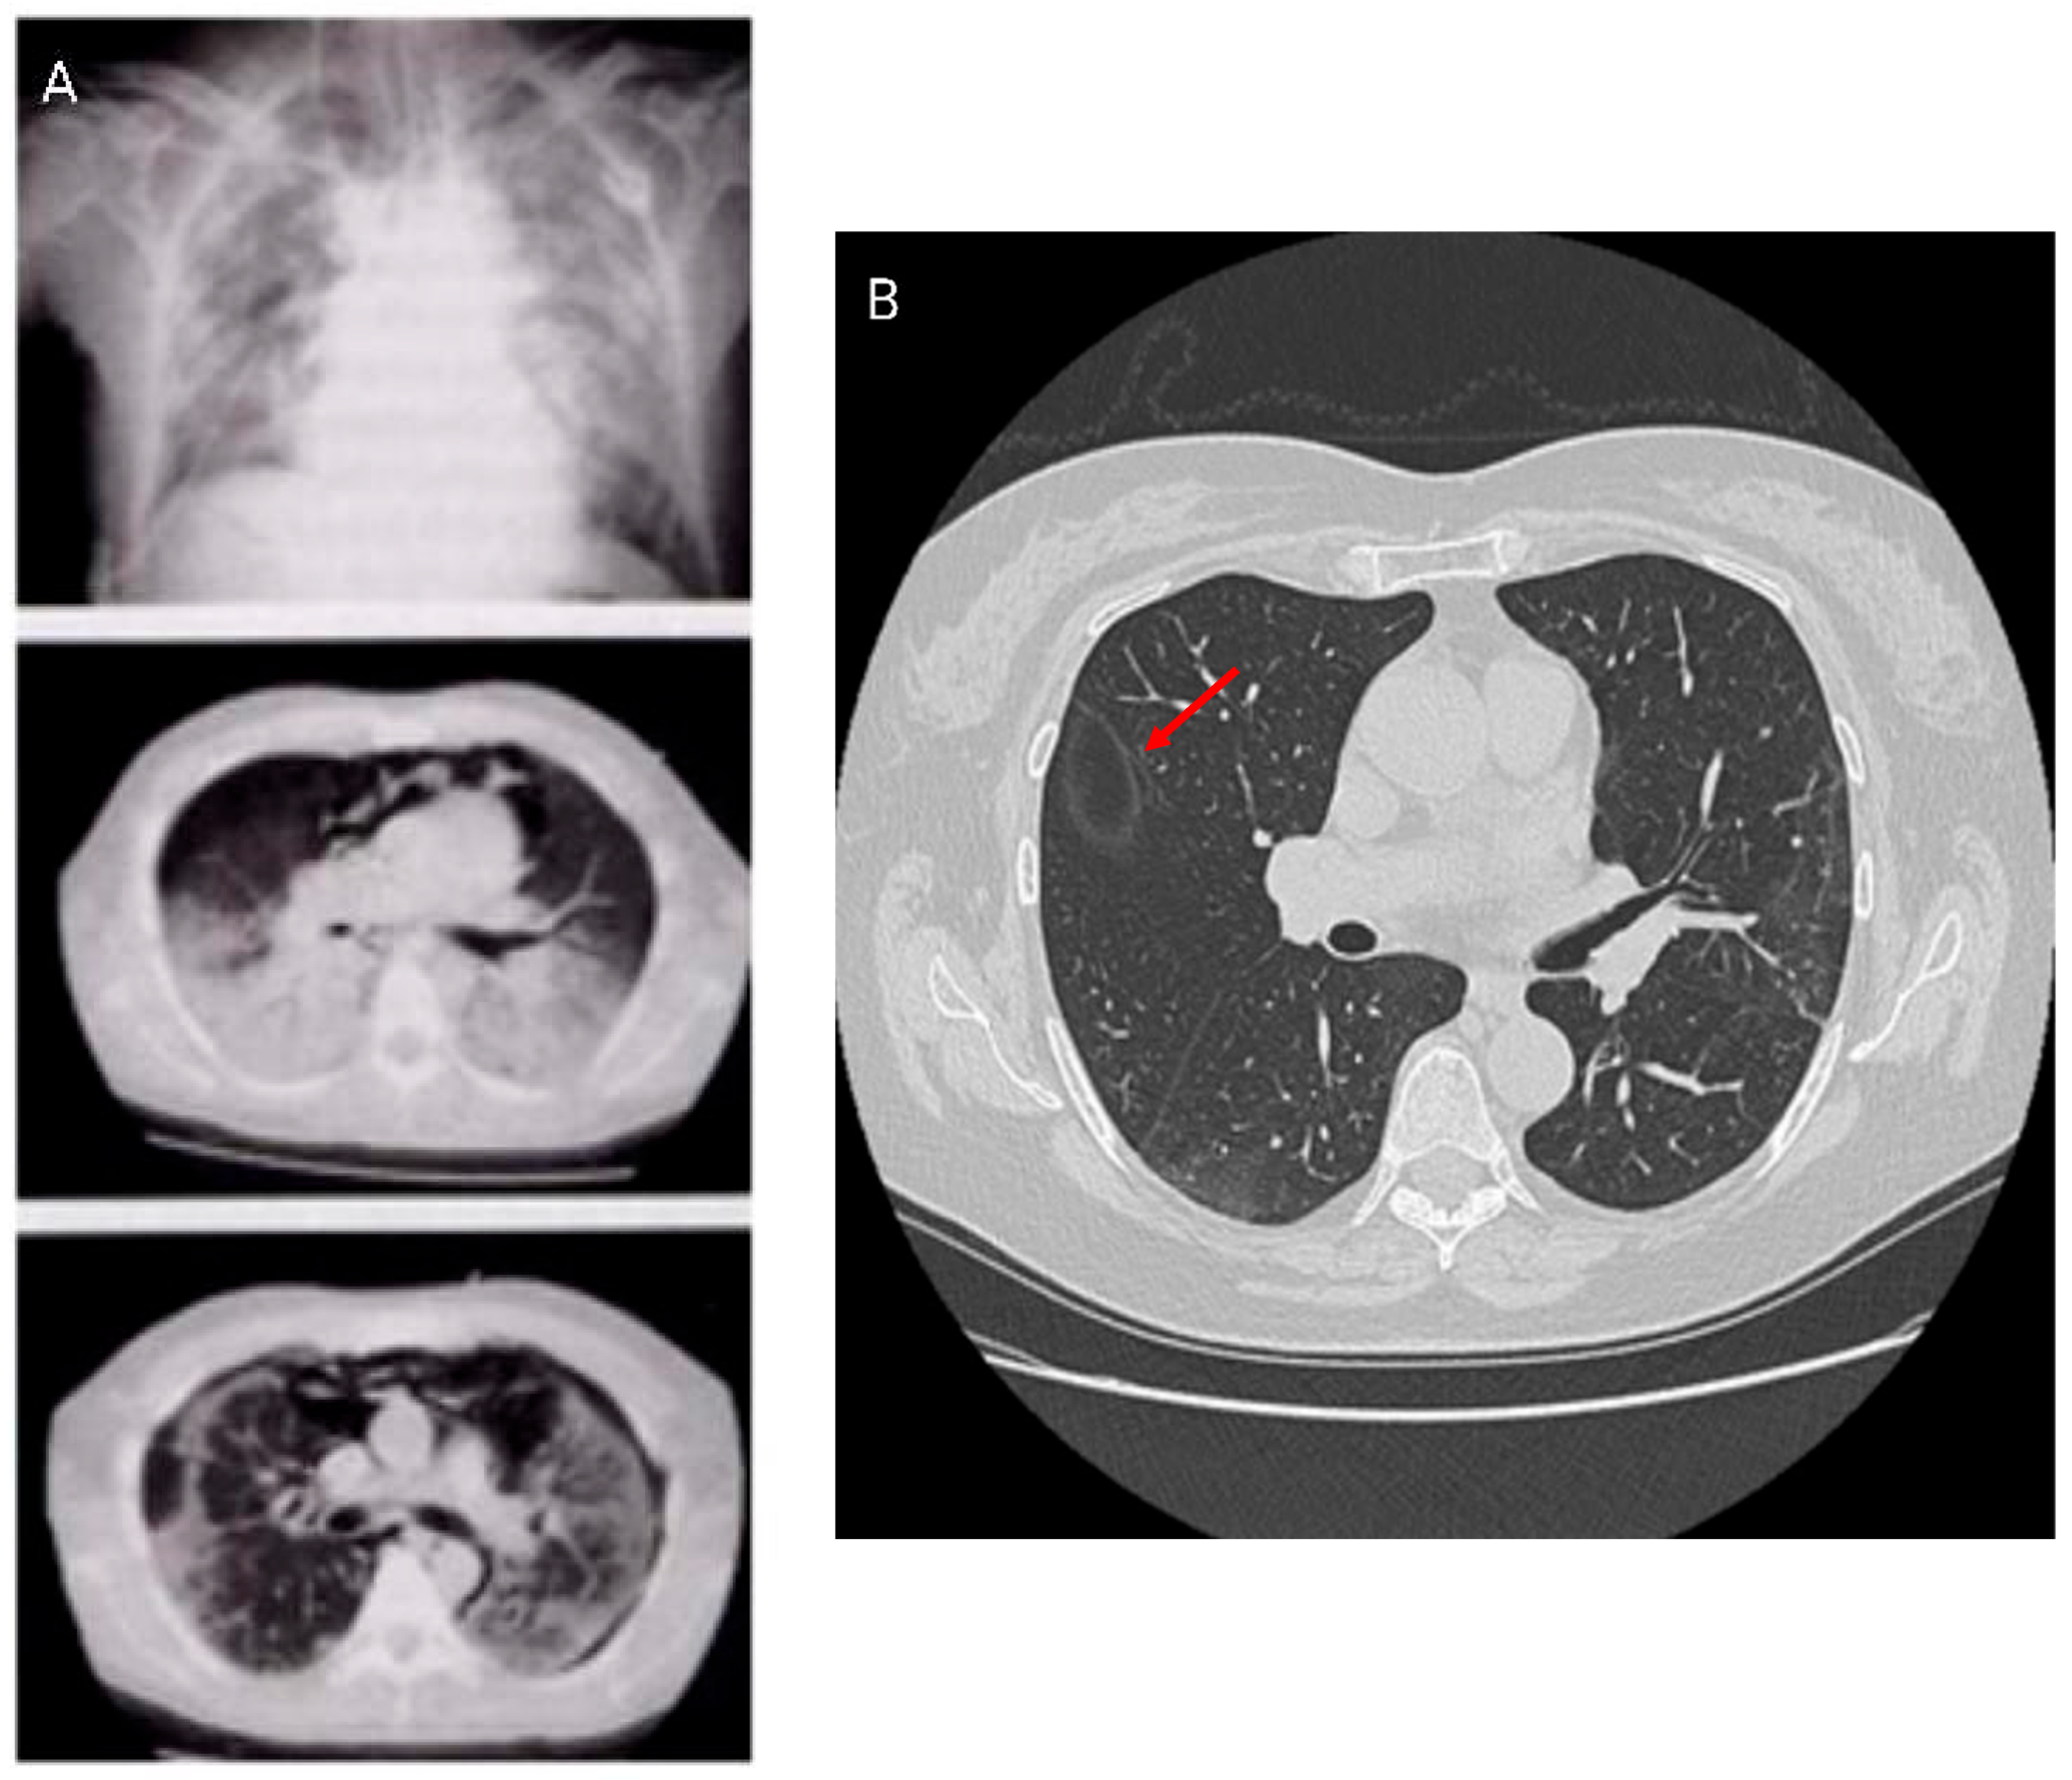

COVID-19 disease is an infection caused by the SARS-CoV-2 coronavirus that may develop subsequent complications involving different organ systems after recovery. These complications include myocarditis, myositis, and brain, kidney, and liver disorders. Pulmonary fibrosis is the major long-term complication of COVID-19 disease (Figure 1).

Figure 1. Picture depicting lung involvement in COVID-19 infection leading to interstitial lung disease.